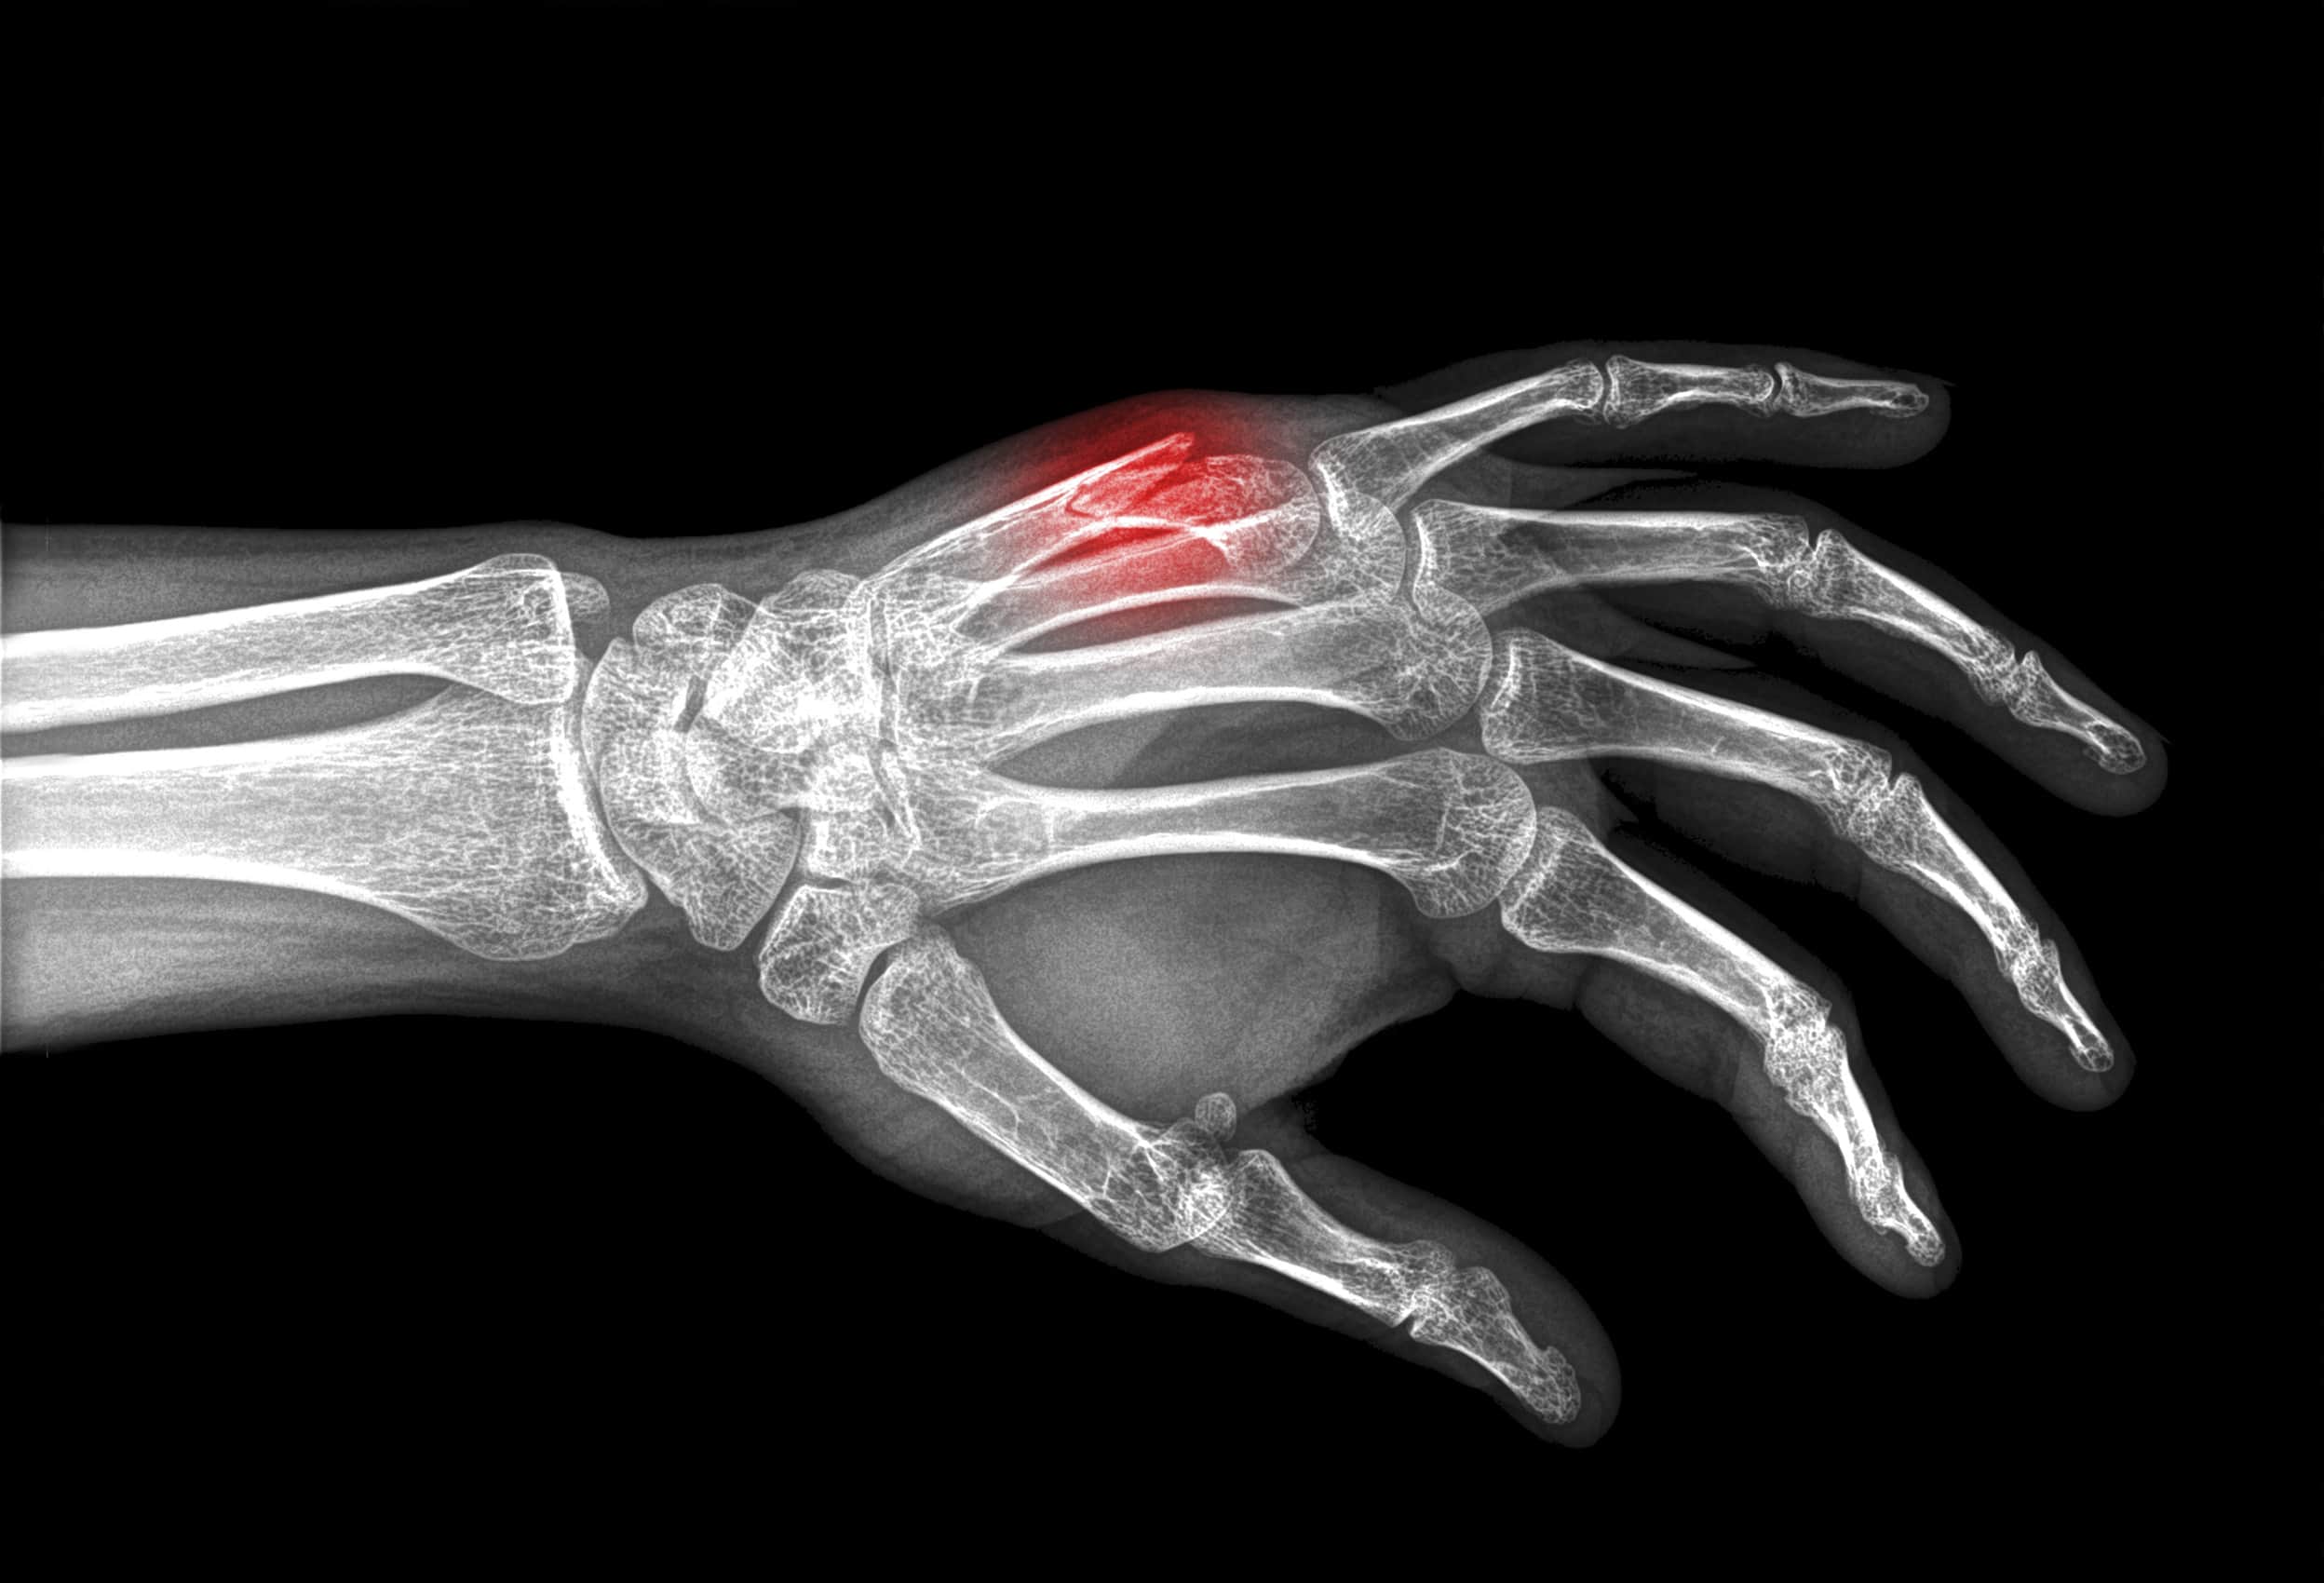

Mittelhandfrakturen gehören zu den häufigsten Handverletzungen und stellen eine bedeutende Herausforderung in der Handchirurgie dar. Diese Frakturen können durch verschiedene Ursachen entstehen, wie Stürze, direkte Gewalteinwirkung oder sportliche Aktivitäten. Das Verständnis der Anatomie, der Frakturtypen, Diagnostik, Behandlungsmöglichkeiten und möglichen Komplikationen ist essenziell, um eine optimale Versorgung sicherzustellen.

Mittelhandknochen Fraktur Symptome, Ursachen, Behandlung

Es erfolgt eine klinische Untersuchung, sowie ein Röntgen, um die Diagnose zu sichern und den Eingriff zu planen. Zudem ist eine CT notwendig, um die Fraktur zu klassifizieren und mögliche Frakturanteile genau beurteilen zu können.